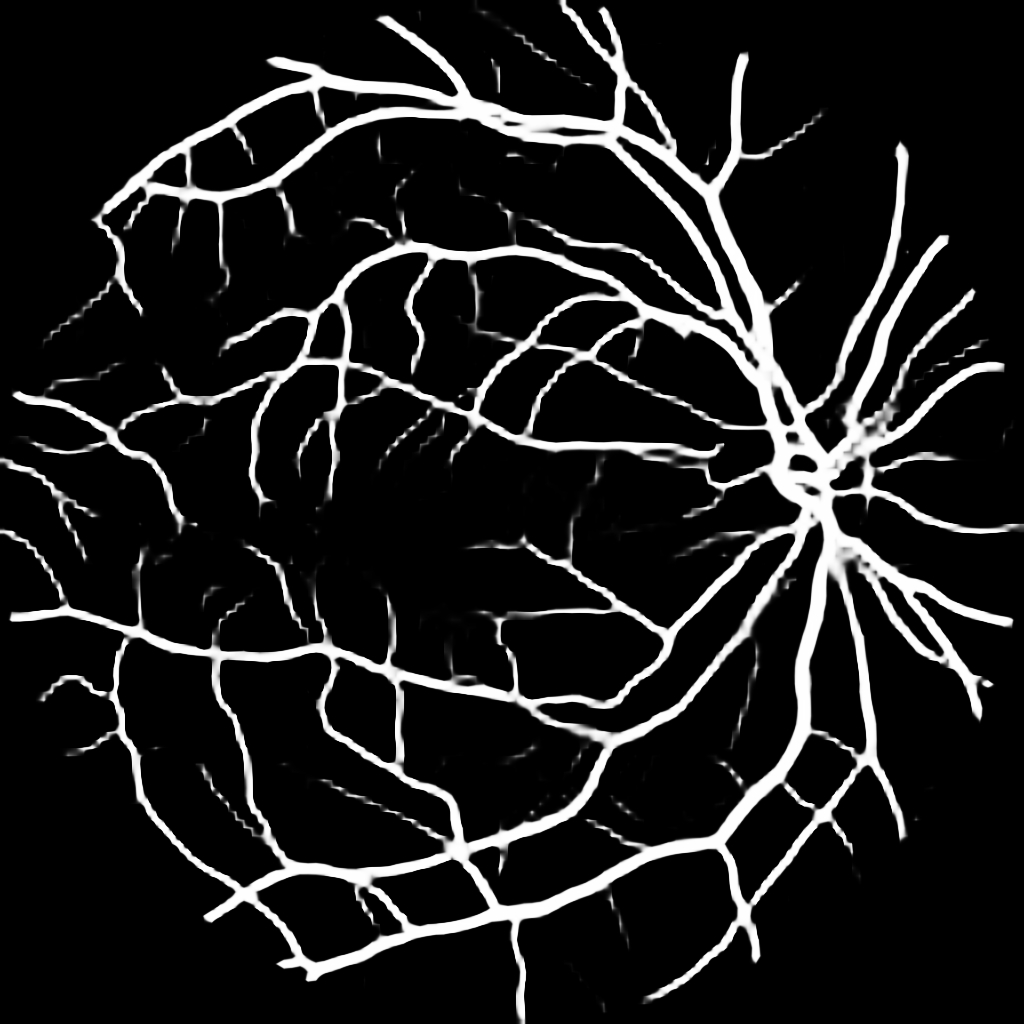

For completeness, and to test the robustness of our method, the models were also tested with several images sourced from Google™. We purposefully sourced extremely poor quality images (i.e. images with low contrast, speckle artefacts, etc), as well as images of pathological cases (i.e. Exdudates, Hemorrhages, etc). As there are no ground truth labels, only a qualitative assessment can be made of the results shown in Figure 2. In all cases, the models have accurately segmented the vessel structure whilst ignoring imaging artifacts and pathological lesions. This is very evident in the case of (5) and (6) where no vessels were segmented in areas of severe hemorrhaging.

{L to R: (1) Healthy, (2) Unhealthy, (3) Speckle Artefacts, (4) NPDR, (5) PDR, (6) Hemorrhages}